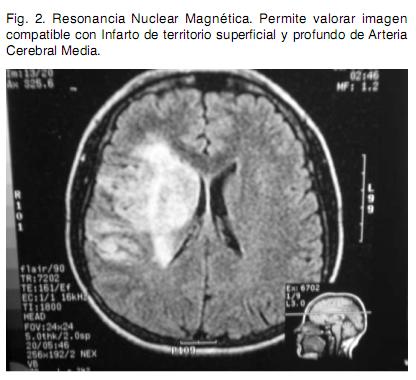

Sexo femenino, 22 años, procedente de medio urbano, diestra, educación primaria completa. Antecedente de migraña de larga data, sin cefalea durante los últimos meses. Destaca en lo ginecobstétrico el consumo de anticonceptivos orales (ACO) combinados y de baja dosis hasta hace tres meses en que se inicia administración de anticonceptivos combinados por vía intramuscular mensual. Dos gestas, dos cesáreas, con nacidos vivos sin complicaciones neonatales; niega historia de aborto espontáneo. Quince días previos a la consulta instala en forma brusca síndrome focal neurológico caracterizado por hemiplejia izquierda total y disartria parética; precediendo al mismo cefalea de predominio en hemicráneo derecho. Se inicia valoración en centro de segundo nivel y se envía en la evolución para completar la misma en centro de referencia. Se realiza Tomografía Computada (TC) de cráneo que informa imagen compatible con ACV isquémico de territorio silviano derecho (Figura 1). Se completa valoración con Resonancia Nuclear Magnética (RNM) que evidencia infarto isquémico en etapa subaguda en territorio superficial y profundo de arteria cerebral media (ACM) derecha, asocia imagen compatible con trombosis de la ACM. El electrocardiograma (ECG) evidencia un ritmo sinusal (Figura 2), con frecuencia de 75 latidos por minuto, P y P-R normales, ventriculografía normal. El Ecocardiograma transtorácico no evidenció alteraciones anatómicas ni trombos en cavidades cardiacas, la Fracción de Eyección del Ventrículo Izquierdo fue de 65%. El Eco Doppler de vasos de cuello informa oclusión de carótida interna derecha de reciente evolución. Arteriografía de cuatro vasos de cuello evidencia disección de carótida interna derecha en el origen y oclusión de ACM derecha en el origen (Figura 3). De la analítica de laboratorio general destaca hemograma, hepatograma, azoemia y creatininemia normales. HIV y VDRL no reactivos. Velocidad de Eritrosedimentación 4 mm en la primera hora. De la valoración de factores de riesgo cardiovascular destaca: Lipidograma con colesterol total de 200 mg/dl, LDL 128 mg/dl y HDL 49 mg/ dl. Glicemia y uricemia normales. Del estudio de la crasis y factores protrombóticos destaca: Tiempo de protrombina de 85%, KPTT 27 segundos, Fibrinógeno 321 mg/dl. Factor V Fig. 1. Tomografía de Cráneo precoz. Destaca imagen compatible con signo de arteria cerebral media hiperdensa (flecha). Fig. 2. Resonancia Nuclear Magnética. Permite valorar imagen compatible con Infarto de territorio superficial y profundo de Arteria Cerebral Media. Fig. 3. Arteriografía de vasos de cuello. Permite visualizar imagen característica de disección arterial (flecha). de Leiden, variante termolábil del gen Metiltetrahidrofolatoreductasa (MTHFR) y FII 20210A, ausentes. Anticuerpos antifosfolipidicos negativo. Del laboratorio de inmunología destaca: Anticuerpos Antinucleares (ANA) 1/40.